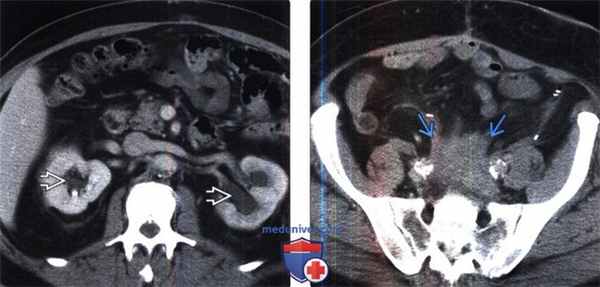

(Слева) КТ с контрастированием, аксиальная проекция: у этого же пациента выявлен двусторонний гидронефроз из-за наличия фиброзной мягкой ткани, показанной на предыдущем изображении.

(Справа) КТ с контрастированием, аксиальная проекция: у того же пациента выявлено атипичное каудальное расширение фиброзного процесса в полость малого таза вдоль подвздошных сосудов.